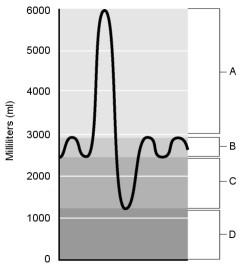

Residual volume.

D

Air that does not participate in the exchange of gases.

D